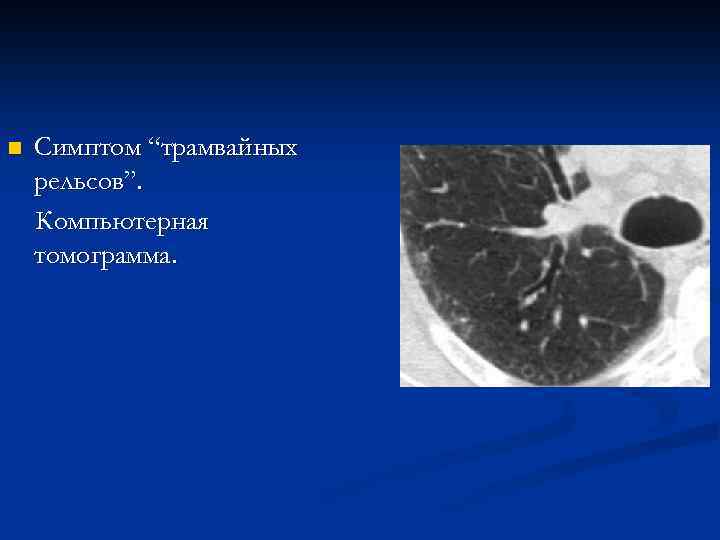

n Симптом “трамвайных рельсов”. Фрагмент рентгенограммы, КТ

n Симптом “трамвайных рельсов”. Компьютерная томограмма.